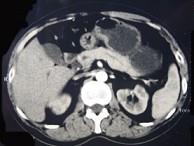

问题 男性,57岁,1年前无明显诱因反复出现嗜睡及发作性神志不清,进食糖水或甜品后症状即缓解,腹部CT检查如下图,最佳的诊断是()

选项 A.胰腺癌 B.胰岛细胞瘤 C.胰腺转移瘤 D.胃泌素瘤 E.舒血管活性肽瘤

答案 B